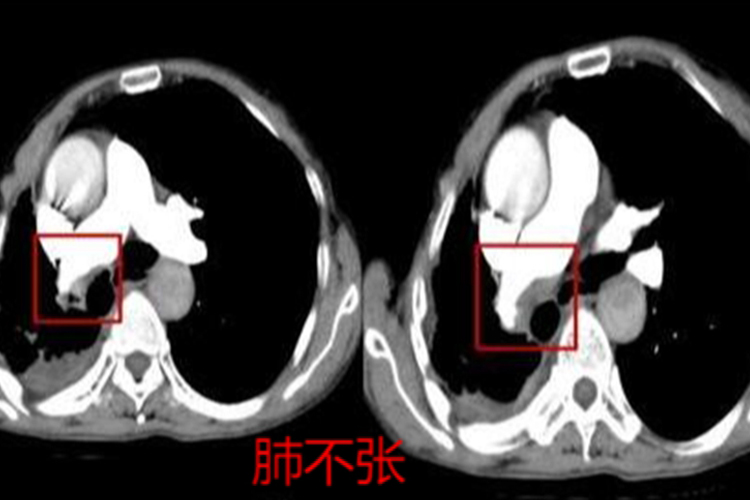

CT具有无创、扫描速度快、图像清晰、较经济的特点,可直观判断肺动脉栓塞的程度和形态,以及累及的部位及范围。肺栓塞直接征象为肺动脉内低密度充盈缺损,部分或完全包围在不透光的血流之内的“轨道征”,或者呈完全充盈缺损,远端血管不显影;间接征象包括肺野楔形条带状的高密度区或盘状肺不张,中心肺动脉扩张及远端血管分布减少或消失等。